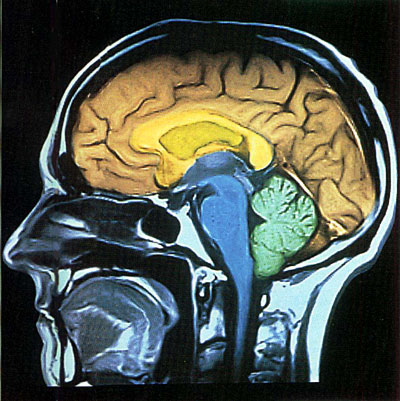

我们的大脑会做梦

梦是生物学领域中的最大奥秘之一。多少年来。这种奇妙的生理现象,一直充满着神秘的色彩,不仅普通人感到困惑难解,就是对于科学家们也展得疑雾重重。然而到1900年,奥地利著名心理学家和精神病医师弗洛伊德开创了“梦学”的研究后,使世界各国的学者们开始正式从心理学、生理学和医学等方面探寻做梦的机制。